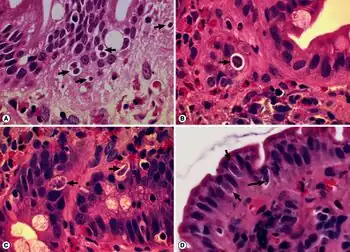

Cystoisospora belli is diagnosed by identification of the oocyst through examining a stool sample under a microscope. The diagnostic stage is the immature oocyst that contains a spherical mass of protoplasm. In other words, the oocyst that is diagnosed in the stool sample is unsporulated, and contains only one sporoblast.[2] For stool diagnosis, direct smear, concentration smear, microscopic wet mount, or iodine stains of fecal smears are adequate. But for easy screening, acid-fast stains is recommended.[2][3] If stool test is negative, and biopsies of the small intestine is performed, different stages of schizogony and sporogony should exist in the epithelial cells, but the alteration of the villi is not necessarily present.[2]